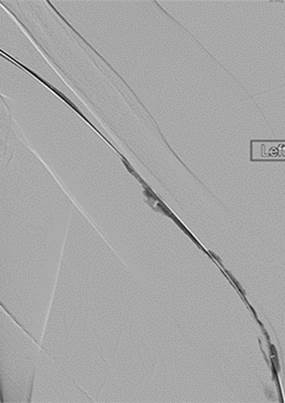

Trombectomía de fístula AV braquiocefálica izquierda

Venograma central inicial que confirma la permeabilidad de las venas centrales.

Estenosis subyacente en el arco de la vena cefálica responsable de la trombosis.